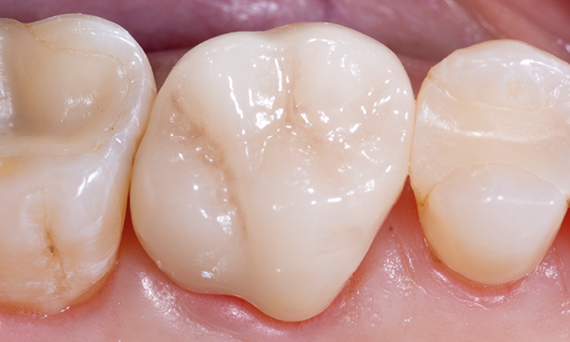

Antes: Insuficiencia grande del relleno de composite en el diente 16 con grietas marginales distales en la cresta, una grieta en la pared lingual y caries recurrente distal.

Después: Corona de vitrocerámica de superficie completa altamente estética.